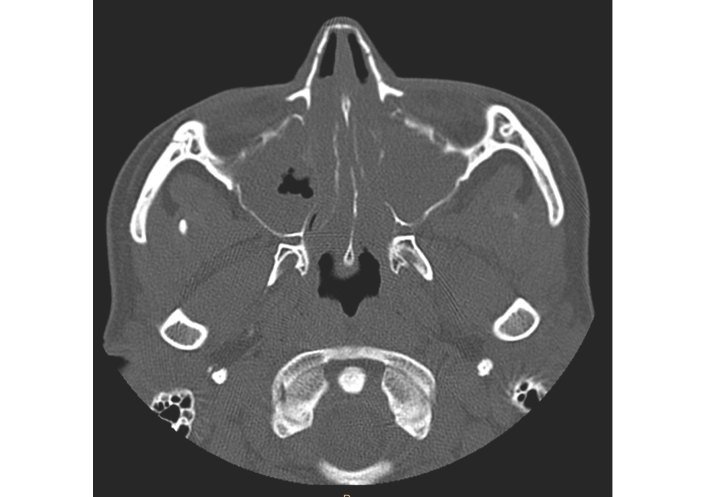

Despite intensive treatment the patient had severe breathing problems and the symptoms significantly impaired the patient’s quality of life. Due to the severe rhinological symptoms, a third sinus surgery was planned. After an insightful differential diagnosis, in accordance with the regulations of the National Health Fund (Appendix B.44), she was qualified for a therapeutic program of biological treatment of severe IgE-dependent allergic asthma using the anti-IgE antibody omalizumab, which at that time was the only available biological drug recommended for the treatment of severe asthma in Poland [10]. A dose of omalizumab 600 mg every 2 weeks was adjusted based on total IgE level and body mass [11]. Surprisingly, already two hours after receiving the first dose of omalizumab, the patient reported improvement in nasal congestion and sense of smell. Before qualification for biological treatment, extensive inflammatory changes were found in the CT scan of the paranasal sinuses (Figure 2). The patient reported a complete loss of smell and a significant increase in rhinological symptoms (Total Nasal Symptom Score [TNSS], 14 points; Sino-Nasal Outcome Test (SNOT)-22, 87 points). In endoscopic examination massive polyposis causing complete obstruction of the nasal cavity was revealed. Nasal polyp score (NPS) was 8 points. Spirometry using the Ganshorn Medizin Electronic spirometer (SpiroScout) revealed severe obturation (FEV1 66%). Our patient’s total IgE was 1,007 IU/mL, and his body mass was 58 kg.

Computed tomography scan of the patient’s paranasal sinuses before biological treatment.